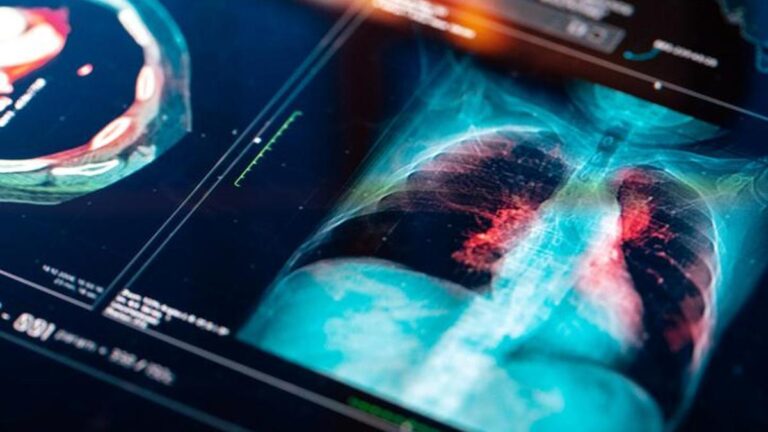

Akciğer kanseri belirtileri nelerdir? Akciğer kanseri nasıl anlanır? Tedavi yöntemleri nelerdir?

Akciğer kanserinin semptomları nelerdir, akciğer kanseri nasıl anlaşılır tedavi yöntemleri nelerdir?Akciğer kanseri nasıl anlanır?

Akciğer kanserini anlamak için semptomlar ilk kez tartışılır. Bu semptomlar, kişiden başlayarak uzman doktorun kontrolü altındaki ön muayene ile sağlanır. Zayıflık, yorgunluk, öksürük anında kanı, kilo kaybı ve iştah kaybı gibi birçok semptom ön plana çıkar. Bu işlemin ardından, prosedür görüntüleme yöntemleri göz önüne alındığında kesin tanı için uygulanır.

Bu nedenle, düşük dozaj akciğer tomografisinin bu anlamda önemli bir yeri vardır. Özellikle erken tomografi ile gerekli tedavi yöntemleri daha etkili olabilir. Ek olarak, kan testleri ve açıklık testleri de pulmoner kanser açısından tartışılmaktadır. Bu nedenle, gerekli tanılarda tartışılan yöntemler birden fazla şekilde kullanılır ve sonuç dahil edilir.